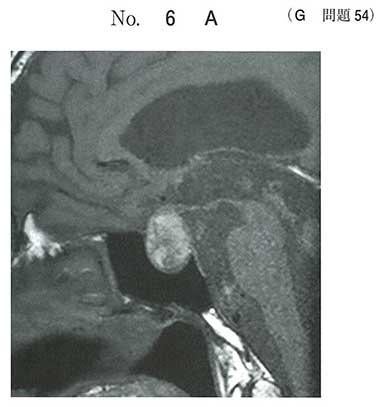

63歳の男性。頭痛と複視とを主訴に来院した。半年前に下腿浮腫、筋力低下、倦怠感および皮膚乾燥があり自宅近くの診療所を受診した。TSH

3.7μU/mL(基準0.4〜4.0)、FT4 0.3ng/dL(基準0.8〜1.8)の検査結果から甲状腺ホルモン補充療法(レボチロキシン50μg/日)が開始された。2ヶ月前から食欲が低下し体重も減少してきていた。今朝、突然に右前額部痛、嘔吐および複視が出現したため救急外来を受診した。意識は清明。身長169cm、体重69kg(2ヶ月前は75kg)。体温36.8度。脈拍80/分、整。血圧154/92mmHg。右眼瞼下垂と右眼球外転偏位とを認める。四肢麻痺はない。頭部単純MRIのT1強調像の矢状断像(別冊No.6A)と冠状断像(別冊No.6B)を別に示す。

基礎疾患として最も考えられるのはどれか。

c 下垂体腫瘍